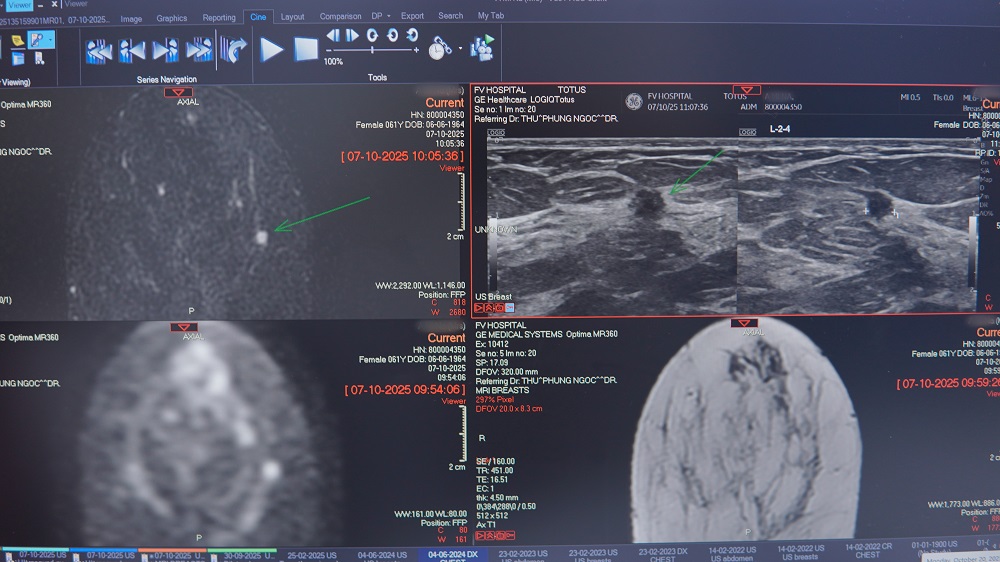

Kết quả nhũ ảnh tìm ra một tổn thương nhỏ, khoảng 7mm ở vú trái. BS.CKI Phùng Ngọc Thư - Trưởng Trung tâm Chăm sóc tuyến vú FV cho bệnh nhân chụp thêm cộng hưởng từ (MRI) do mô vú của bà A. khá đặc. Qua phim chụp MRI, bác sĩ Thư phát hiện thêm một nốt tổn thương khác, chỉ 3mm.

“Khối u 3mm này quá nhỏ nên trên nhũ ảnh không thể bộc lộ, ngay cả trên MRI nó cũng chưa thể hiện rõ đặc điểm ác tính, dễ bị bỏ sót hoặc cho qua” - bác sĩ Thư giải thích.

Phát hiện tổn thương 7mm ở vú trái bằng chụp nhũ ảnh - Ảnh: FV

Hình chụp MRI cho thấy một tổn thương 3mm - Ảnh: FV